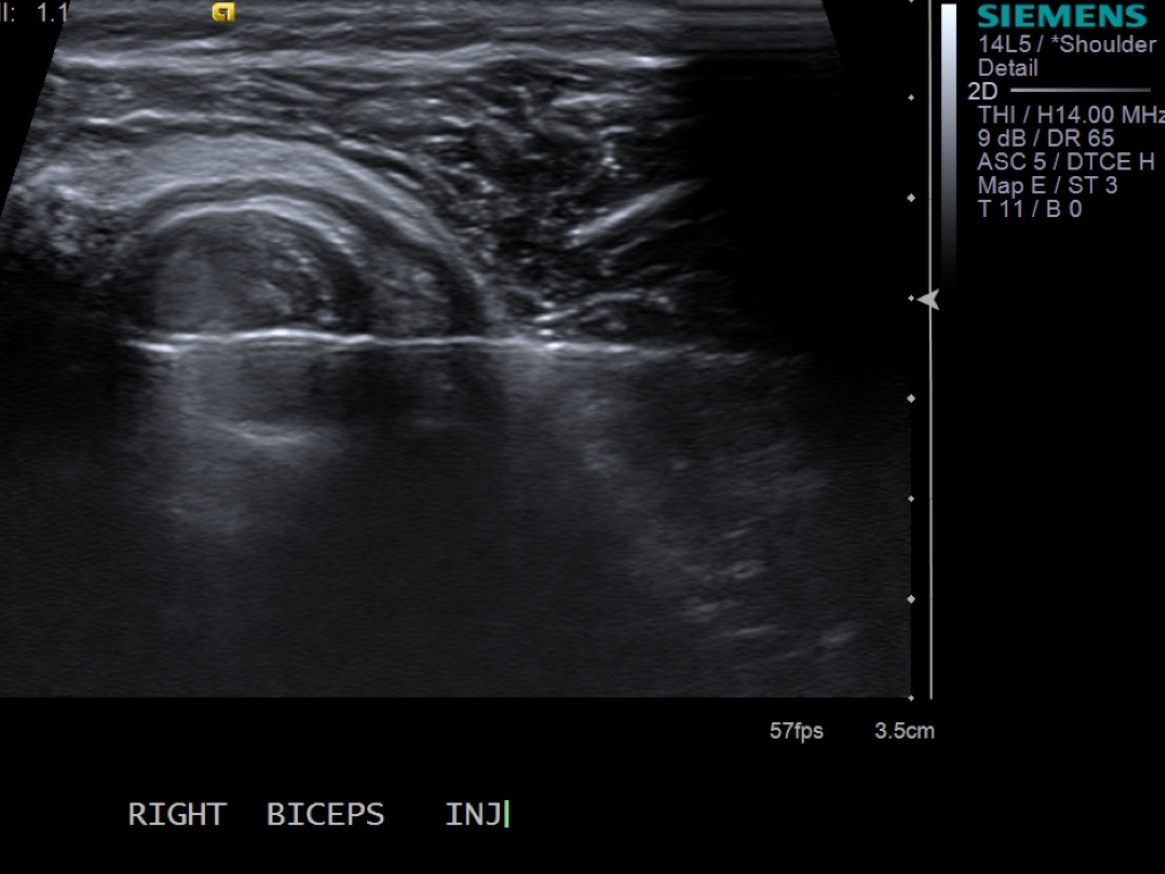

3. Scan patient looking at the biceps tendon (short axis/transverse) extra-articular and at the rotator interval. If there is fluid in the biceps tendon sheath when extra-articular, you can inject at that site. Otherwise, will need to inject at the rotator interval.

Extra-articular biceps tendon in transverse plane

10. With ultrasound guidance, advance the 25g needle into the sheath surrounding the tendon.